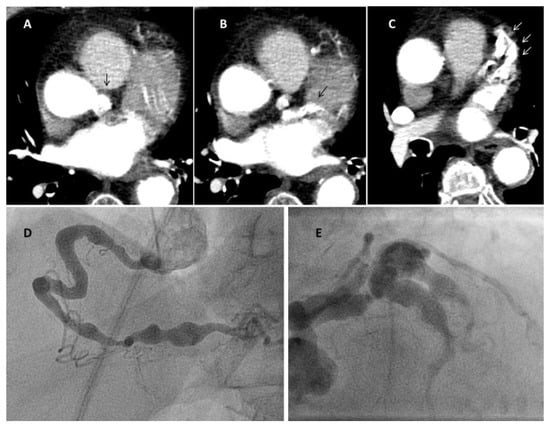

At angiography, coronary artery vasculitis may manifest under the form of coronary stenosis, aneurysm (Figure 2), dissection (Figure 3, most frequent in eosinophilic periarteritis), spasm (Figure 4), or coronary rupture (Table 1). Sudden death, typical angina, acute myocardial infarction, atrial and ventricular arrhythmias, conduction disturbances, or cardiac failure have all been described []. Although no specific finding at coronary angiography allows a safe diagnosis, features associated with early, advanced, or atypical coronary artery disease may suggest an inflammatory etiology. For example, Kawasaki disease and polyarteritis nodosa are often associated with large aneurysms []. Polyarteritis nodosa often features multifocal aneurysms with a “beads on a string” or nodular appearance [], which are also present in patients with anti-neutrophil cytoplasmic antibody (ANCA)-associated vasculitis and Behcet’s disease []. The arterial lesions in Behçet disease may be occlusive or aneurysmal []. Giant cell arteritis has been associated with long coronary lesions [], and in Takayasu’s arteritis, coronary lesions have been classified in three main types: 1, stenosis or occlusion of the coronary ostia (60–80%); 2, diffuse disease that may involve all epicardial branches or only focal segments (10–20%); and 3, coronary aneurysms (0–5%) [].

Figure 2.

Coronary aneurysms in an 80-year-old female patient with stroke and rheumatoid arthritis. Panel a: right coronary; Panel b: left coronary (arrows mark the aneurysms). The patient had been admitted for sudden loss of consciousness. Chest computed tomography (panels A–C, Video S1) was performed for the suspect of lung embolism. The exam showed severe coronary aneurysms. At angiography (panel D,E), the aneurysms were so large that they could not be imaged in one single run despite large contrast volume.